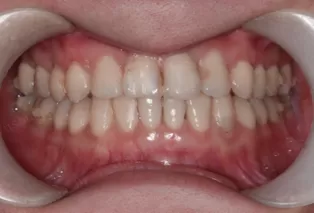

Photos intra-orales